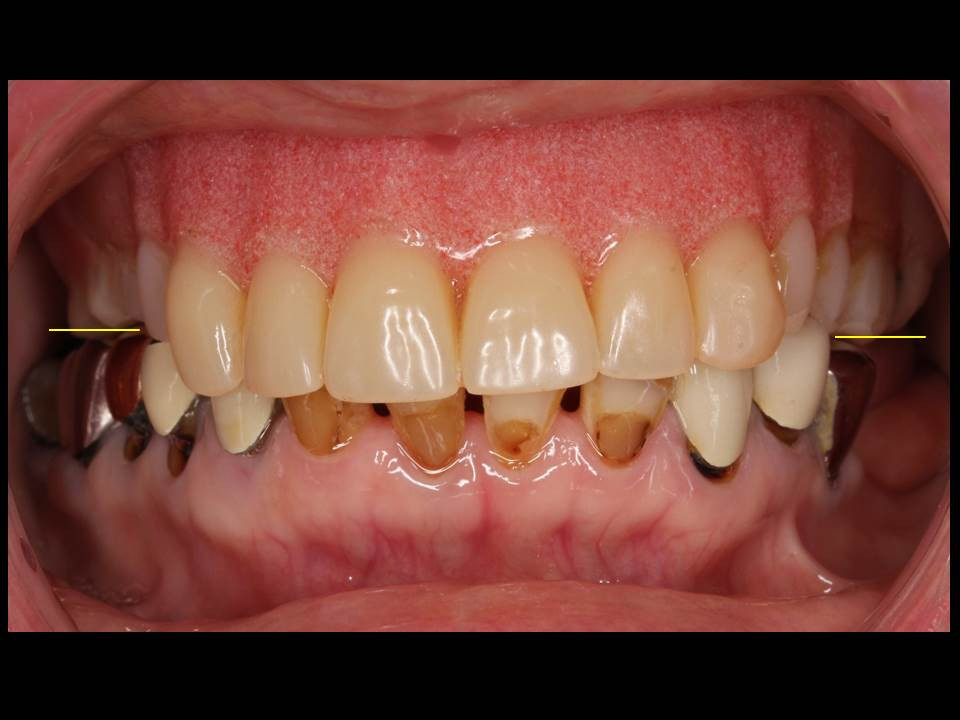

噛み合わせと歯並びが乱れています。

術前のお口の中の様子①

今回の患者様は長く合わない入れ歯を使用し、むし歯と歯周病により、咬み合わせのバランス、見た目の面での美しさが失われ、摂食嚥下能力が落ち、「口腔機能不全」の状態でおりました。正面から歯並びを見た写真では、奥歯の高さが左右で異なっており、上の前歯が下がり過ぎている状態でした。